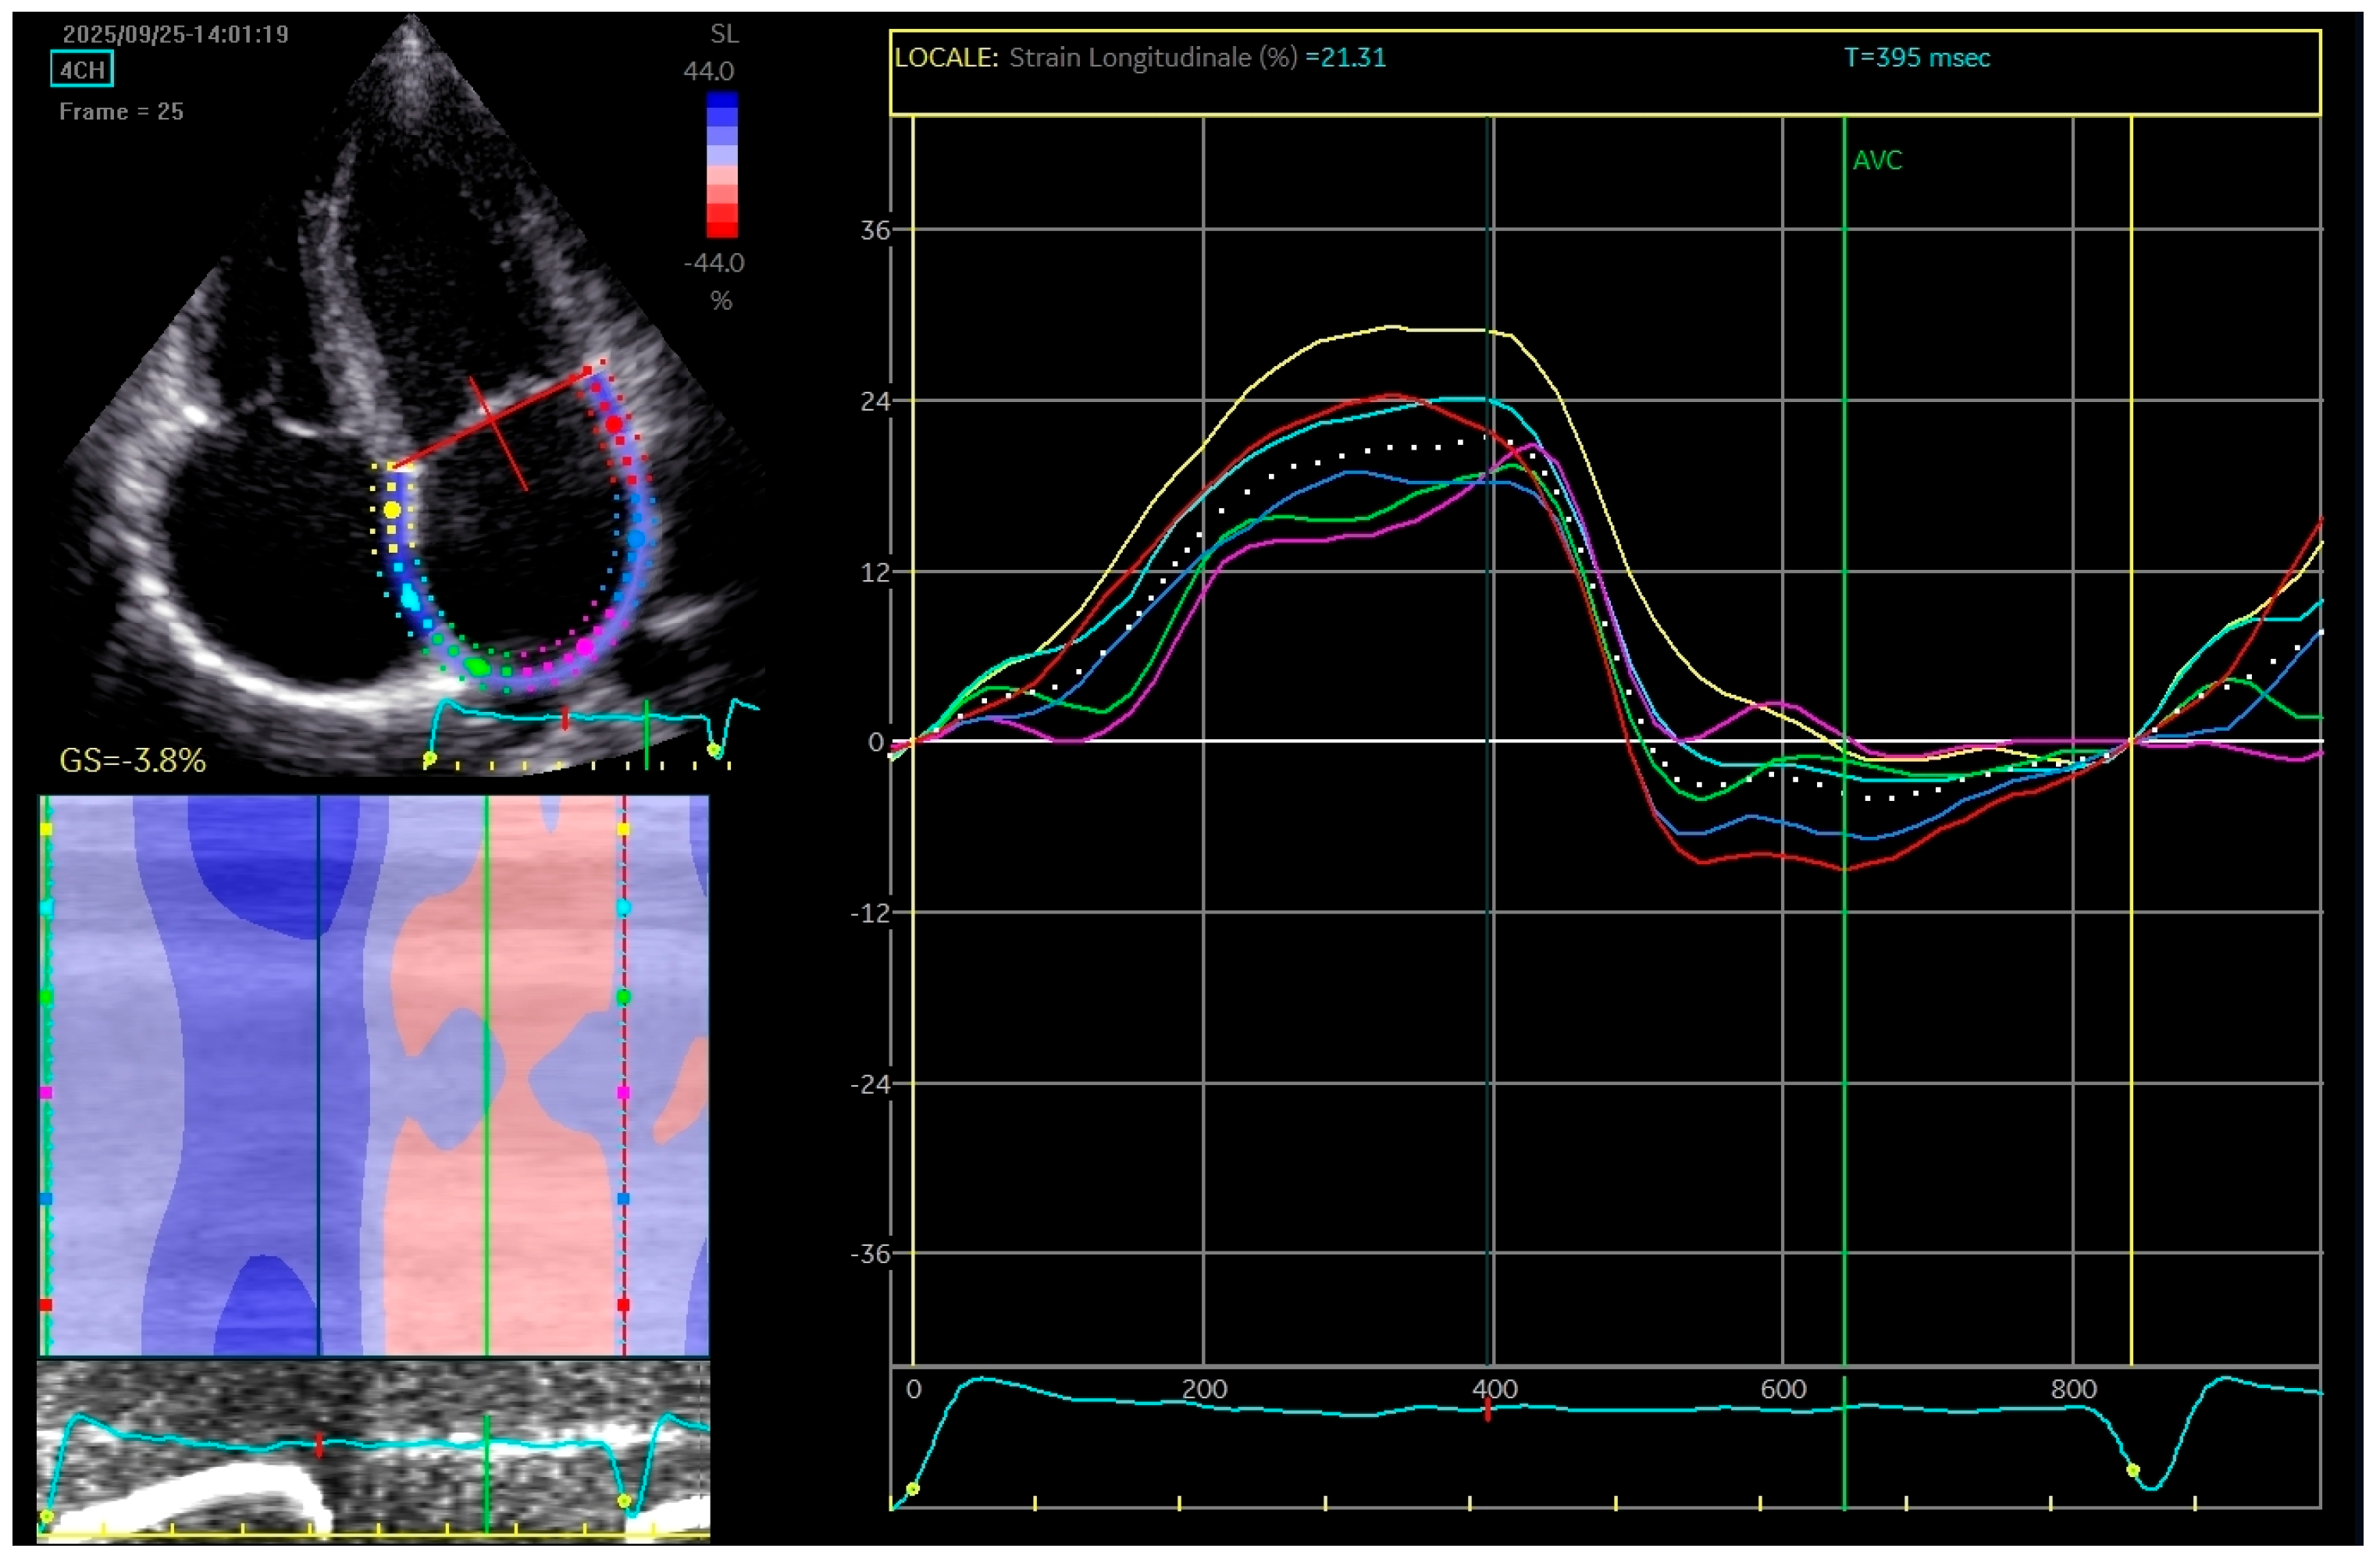

Two-dimensional speckle tracking echocardiography was conducted, revealing a mild reduction in left atrial function based on strain and strain rate parameters, which indicates increased stiffness of the atrium (Figure 3).

Figure 3. The apical four-chamber view was utilized for the strain measurements of the left atrium (LA); the edge of the LA endocardium was manually traced. The software generated tracings based on the 2D strain of LA. The mean deformation (strain) is expressed in percentage and calculated by the software.